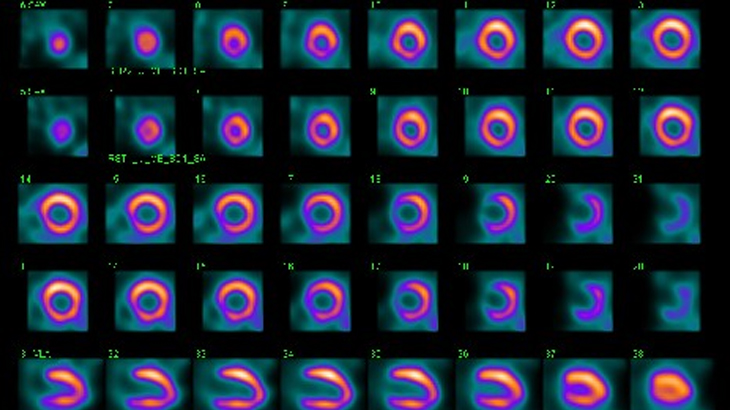

Nuclear cardiology is a branch of nuclear medicine that uses a tiny amount of radioactive material (radioactive tracer) to study the heart. Pictures taken with the radioactive material and a special camera will show both blood flow to the heart muscle and its pumping function.

- Imaging test to evaluate blood flow to the heart muscle (myocardial perfusion imaging)

- Imaging test to evaluate pumping function of the heart (gated perfusion imaging)

Myocardial perfusion imaging (MPI)

Myocardial perfusion imaging (MPI) involves the use of a radioactive tracer to evaluate blood flow to the heart muscle. While cardiac CT angiography and cardiac catheterization diagnose the presence and severity of coronary artery disease, myocardial perfusion imaging diagnoses the effect of coronary artery disease on the blood flow to the heart muscle. Insufficient blood flow to the heart muscle causes chest pain or other symptoms experienced by patients with significant coronary artery disease.

Gated perfusion imaging

Gated perfusion imaging evaluates motion of the heart muscle and how well the heart is pumping, which is measured as percent LVEF (left ventricular ejection fraction). This is performed at the same time as myocardial perfusion imaging using a special computer program. Therefore, both blood flow and pumping function of the heart are evaluated in one study and, in the majority of cases, in one visit.

The nuclear medicine division has acquired a new SPECT camera called D-SPECT (Dynamic SPECT), an innovative solid state design camera.

- High-speed imaging: 10 times more efficient Gated SPECT imaging can be completed in as little as two minutes without compromising image quality. The imaging time can be reduced from 40 minutes or more to 6 minutes or less.

- High-quality images due to twice the imaging resolution of the current conventional SPECT cameras.